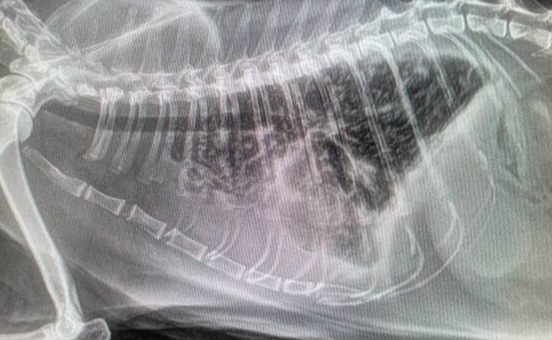

Дано: возрастная кошка с длительным ринитом.

Пришли на прием 13.10 с формулировкой «гноится глазик». Я увидел их 14.10 и всё же уговорил пойти на кт, а там абсцесс за левым глазом, фронтит (забиты и лобные пазухи, и носовые ходы).

После проводим фронтотомию - по сути, бурим дырку в лобную пазуху для промывания и вымывания всего скопившегося гноя.

Промыв всё большим количеством тёплого стерильного физ.раствора, зашиваем всё. Плюсом удаляем назофарингеальный полип.